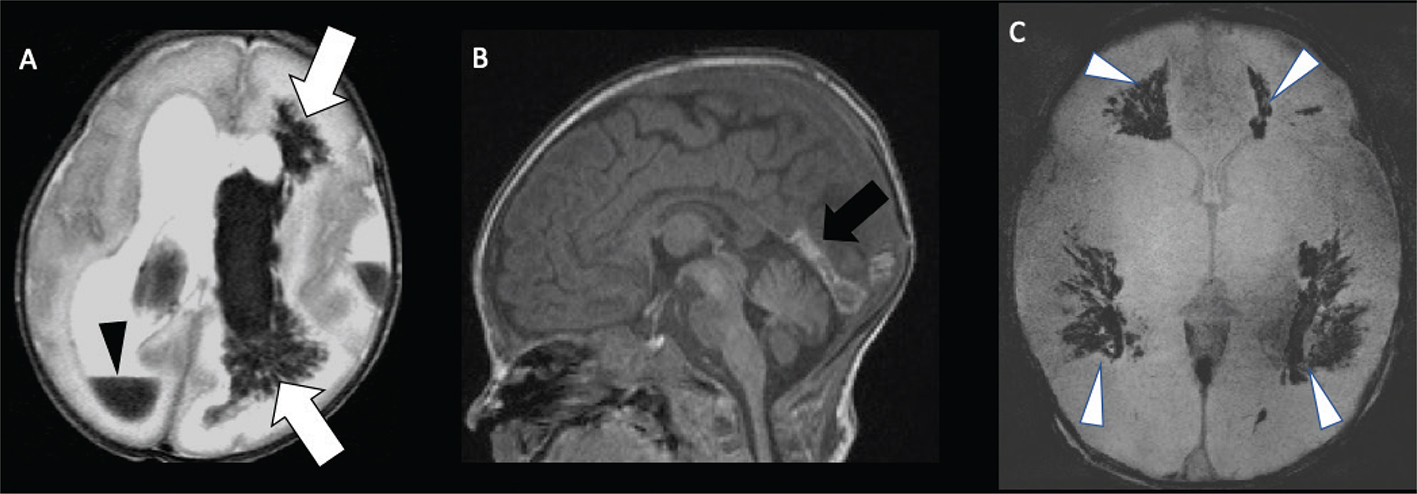

Periventricular venous infarction occurs in preterm infants as a consequence of germinal matrix hemorrhage, typically prior to 32 weeks of gestation (11). Germinal matrix hemorrhage may secondarily cause compression of the medullary veins, resulting in focal venous infarction in the periventricular white matter (100). Primary thrombosis of deep medullary vein can also be seen in full term neonates with congenital heart disease or with dehydration/metabolic acidosis, in the absence of germinal matrix hemorrhage, hypothesized to be related to hypoperfusion or impaired cerebral blood flow, and resulting in periventricular white matter venous infarct, often hemorrhagic (101103). The “iris sign,” a fan-shaped appearance of restricted diffusion or hemorrhage, most prominent in the deep frontal white matter, is a pathognomonic imaging sign of medullary vein thrombosis (Figure 10) (104). Delayed findings of periventricular venous infarction include periventricular white matter volume loss sparing the cortex and basal ganglia, focal irregularity of the ventricular margin, and hemosiderin staining (105). If spontaneous venous thrombosis is identified, the patient should be evaluated for disorders of coagulation (30, 97, 106113).

Fig 10

Figure 10. Medullary vein thrombosis and periventricular venous infarctions. Ex-premature at 32 weeks of gestation neonate, axial T2-weighted image (A) shows intraventricular hemorrhage (Black arrowhead), medullary veins thrombosis, and periventricular venous infarctions (arrows). A 7-day-old full-term neonate with severe dehydration. Sagittal T1-weighted (B) and axial GRE (C) images shows acute thrombus in the straight sinus (black arrow) and torcular and extensive thrombosis of the deep periventricular medullary veins (white arrowheads). Case courtesy of Dr. Tamara Feygin, Department of Radiology, Children’s Hospital of Philadelphia.